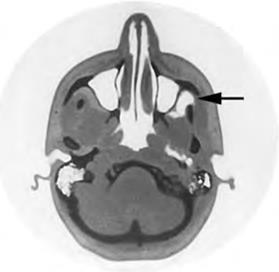

Рис. 1.3. Анестезия подглазничного нерва:

а – внеротовой доступ; б – внутриротовой доступ

Подглазничное отверстие, являющееся ориентиром при проведении анестезии, проецируется на кожу лица на 0,5 см ниже края глазницы и соответствует линии, проведенной через центр зрачка глаза, смотрящего вперед. Этот вид анестезии может быть выполнен внеротовым и внутриротовым доступами.

Внеротовой доступ: пальпаторно определяют нижний край глазницы, обнаруживают желобок, соответствующий месту соединения скуловой кости со скуловым отростком челюсти и, растянув кожу между1и2пальцами левой руки, вкалывают иглу, отступя на 0,7 см вниз от края глазницы. Иглу продвигают вверх и кнаружи по направлению к кости. Достигнув ее поверхности, не проникая иглой в канал, выпускают анестезирующий раствор. Обезболивание наступает через 2 – 3 мин (рис. 1.3, а).

Внутриротовой доступ: 1 и 2 пальцами левой руки отводят верхнюю губу кверху и кнаружи, а средним пальцем фиксируют место проекции нижнеглазничного отверстия, которое при внутриротовом доступе находится на пересечении двух линий – горизонтальной, проходящей на 0,5 – 0,75 см ниже нижнеглазничного края, и вертикальной, проходящей по оси второго верхнего премоляра соответствующей стороны. Иглу вкалывают на 0,5 см кверху от края прикрепления переходной складки между средним и боковым резцами и продвигают ее вверх, вперед и кнаружи по направлению к нижнеглазничному отверстию до упора в поверхность кости, где и инъецируют анестетик (см. рис. 1.3, б).